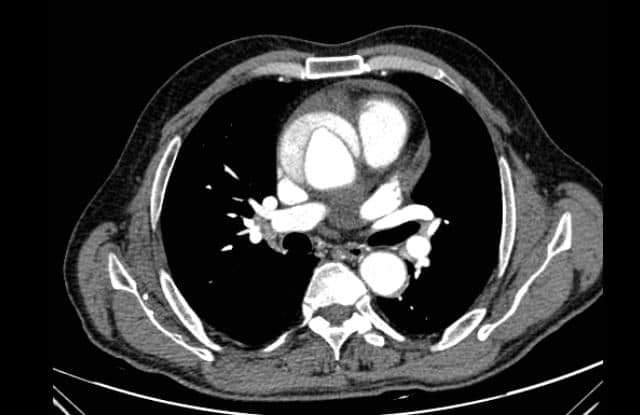

أجرى فريق طبي من قسم جراحة القلب والصدر بكلية طب بني سويف، في حدث فريد من نوعه بقيادة الدكتور جهاد محمد مصطفى استشاري جراحة القلب والصدر، جراحة طارئة لمريض يعاني من انشقاق بالشريان الأورطي الصاعد، وهذه الحالة غاية في الخطورة حيث تتسبب في وفاة المريض خلال ساعات قليلة جدًّا إذا لم يتم إجراء جراحة طارئة له، وهذه خدمة جديدة تقدمها مستشفيات جامعة بني سويف لمرضى المحافظة.

وتعتبر هذه الجراحة غاية في الدقة والخطورة، حيث تم استبدال الصمام الأورطي والشريان الأورطي الصاعد وإعادة زرع الشرايين المغذية للقلب بالشريان الأورطي الصناعي.